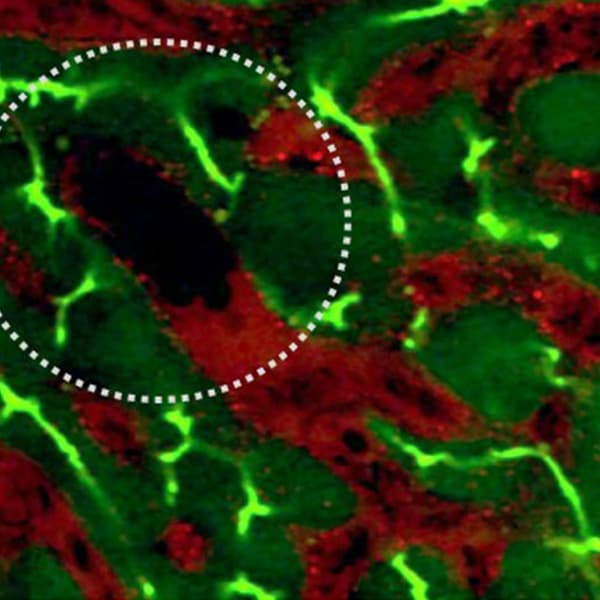

Intravital imaging of sickle cell mouse liver . In red Texas red dextran and Carboxyflurescein is in green. Circled area shows vasoocclusion.

Intravital imaging of sickle cell mouse liver. In red Texas red dextran and Carboxyflurescein is in green. Circled area shows vasoocclusion.